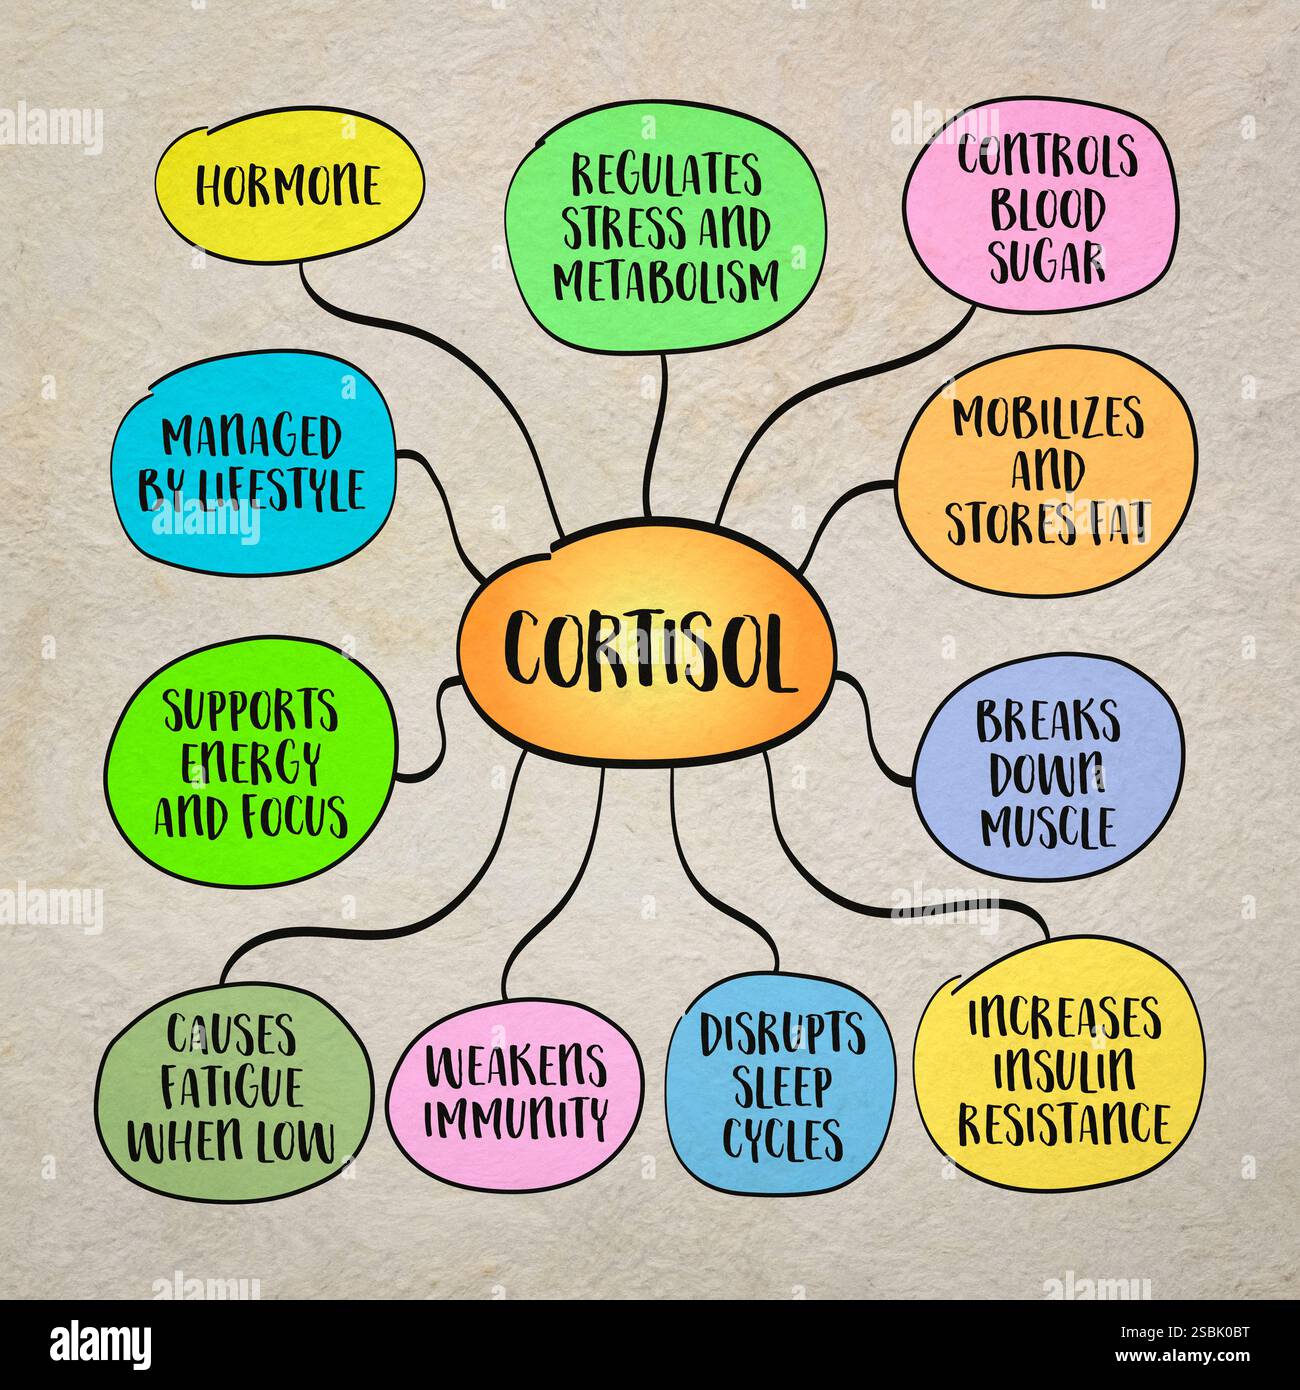

RF2SBK0BT–Le cortisol, hormone du stress, joue un rôle crucial dans le métabolisme, la régulation de l'énergie, la fonction immunitaire et la santé globale. Croquis infographique.